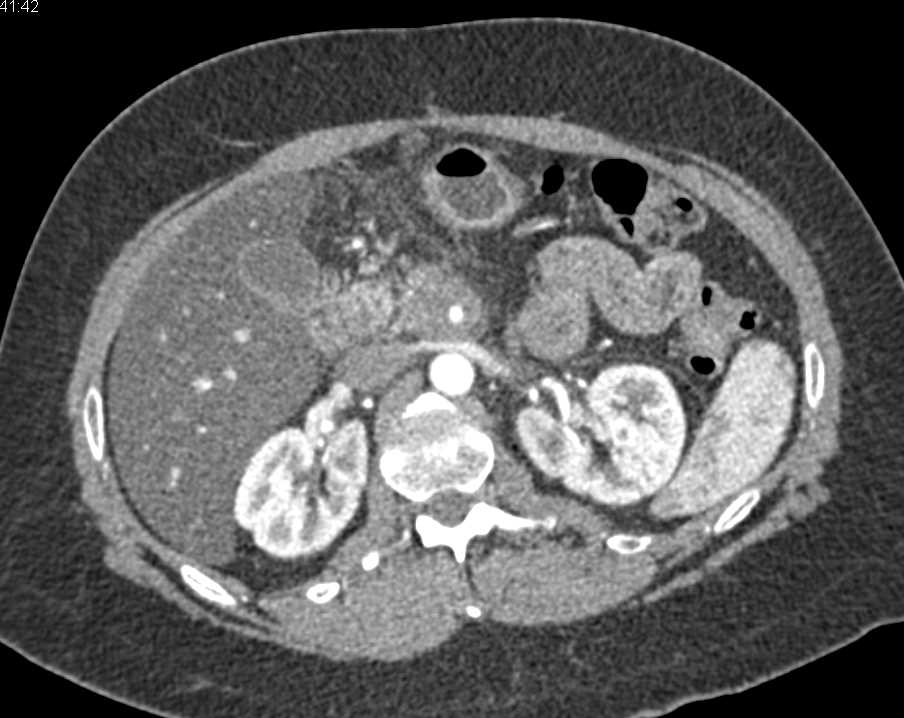

Pancreatic Adenocarcinoma Involves the CBD